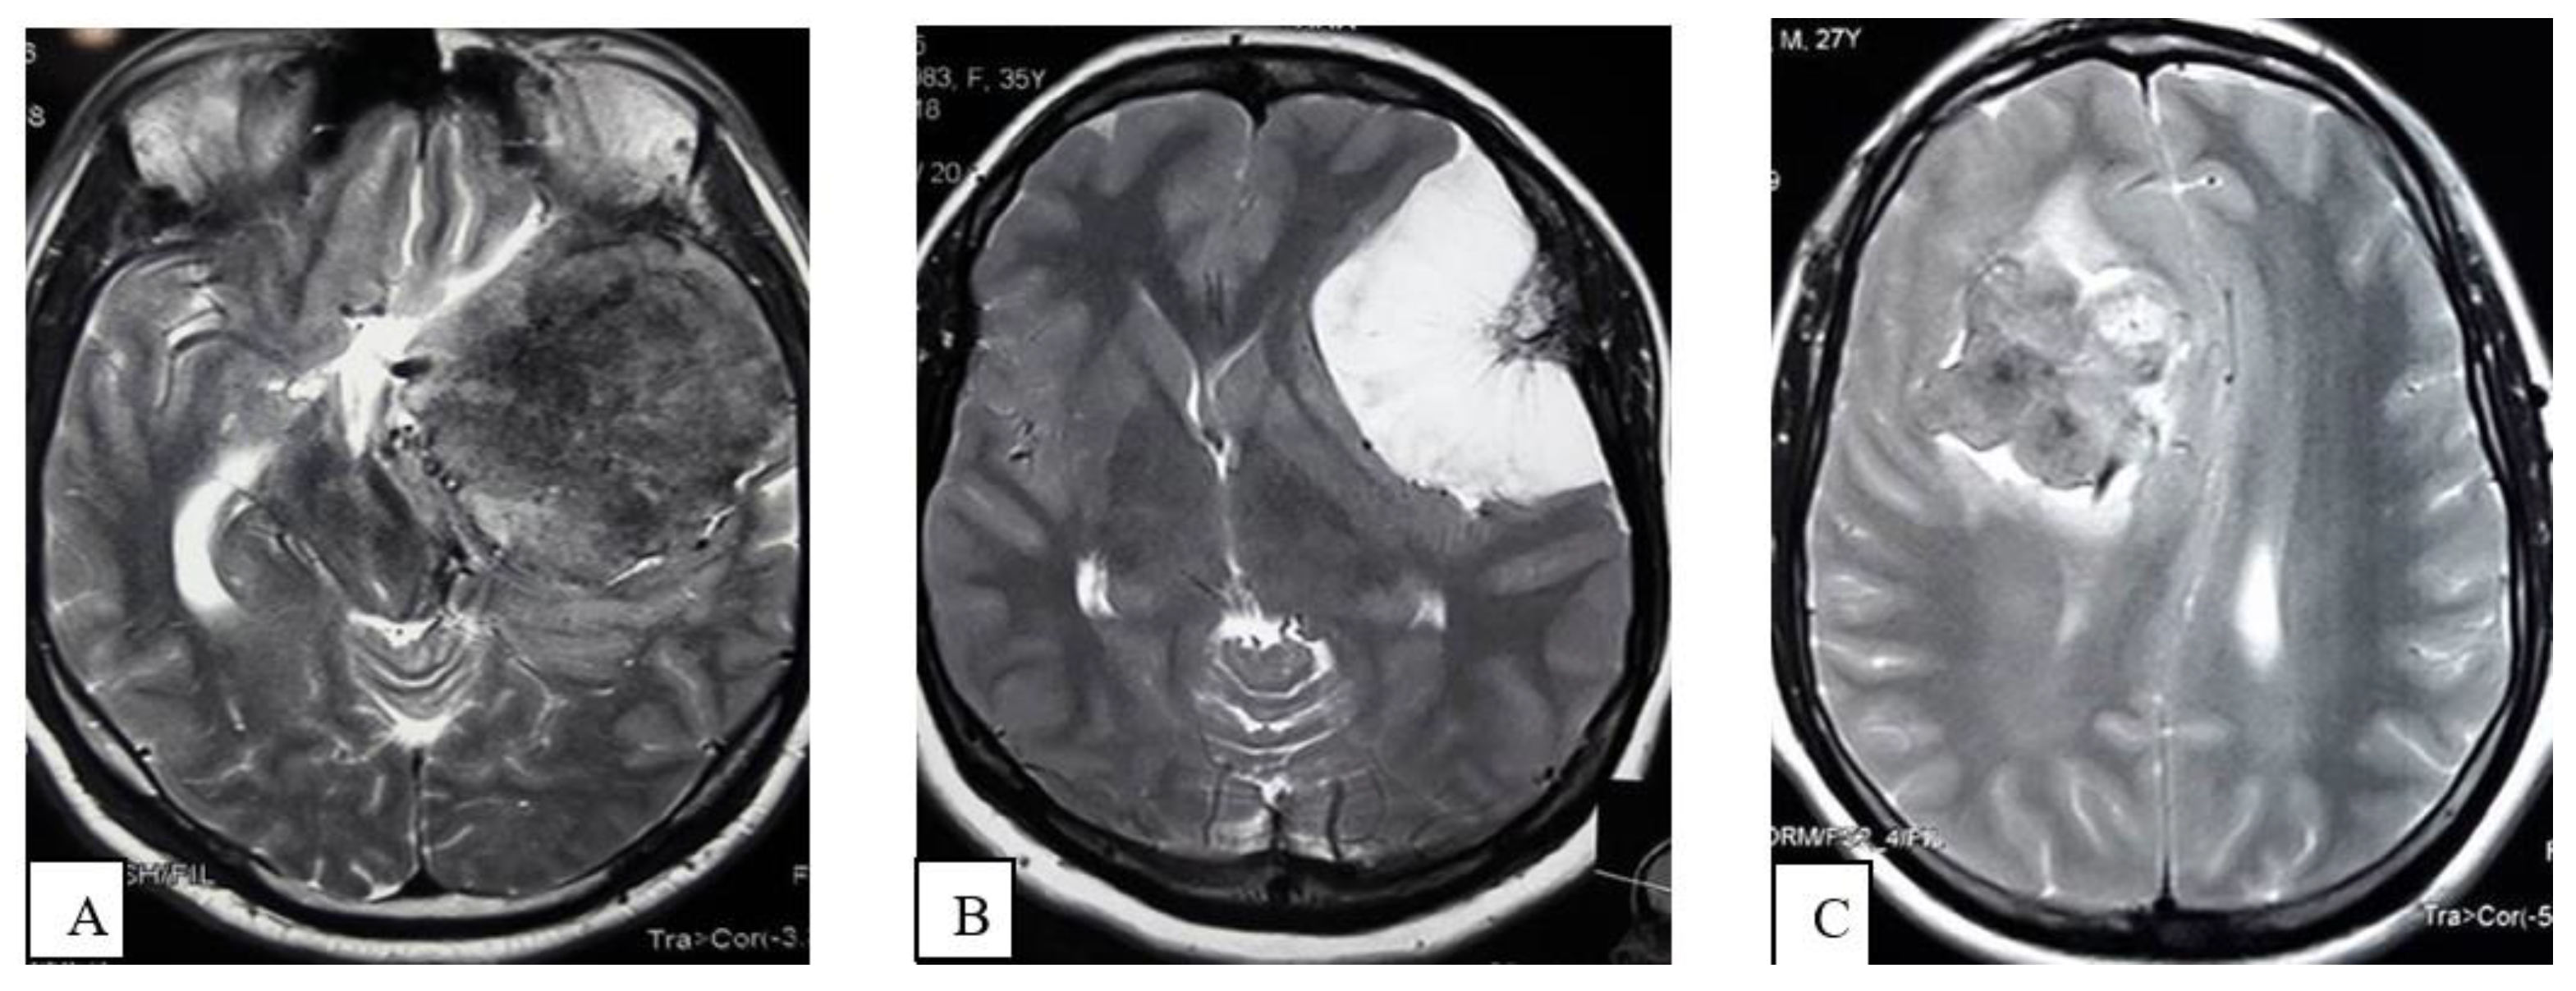

- Extrapial: Surgical cleavage plane lies outside the pia mater in more than two-thirds of the overall interface between tumor and cortex, regardless of whether an arachnoid membrane could be clearly identified (Figure 4A);

- Mixed: Cleavage plane lies outside the pia mater in more than one-third but less than two-thirds of overall interface (Figure 4B);

- Subpial: Tumor capsule exceeds the pia mater in more than two-thirds of the tumor cortex interface, and the surgeon was required to pass underneath the pia mater because of its incorporation into the tumor capsule (Figure 4C).